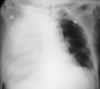

Инфильтрат нижней доли левого легкого

Альвеолярный инфильтрат в нижней доле левого легкого у пациента с бактериальной пневмонией.